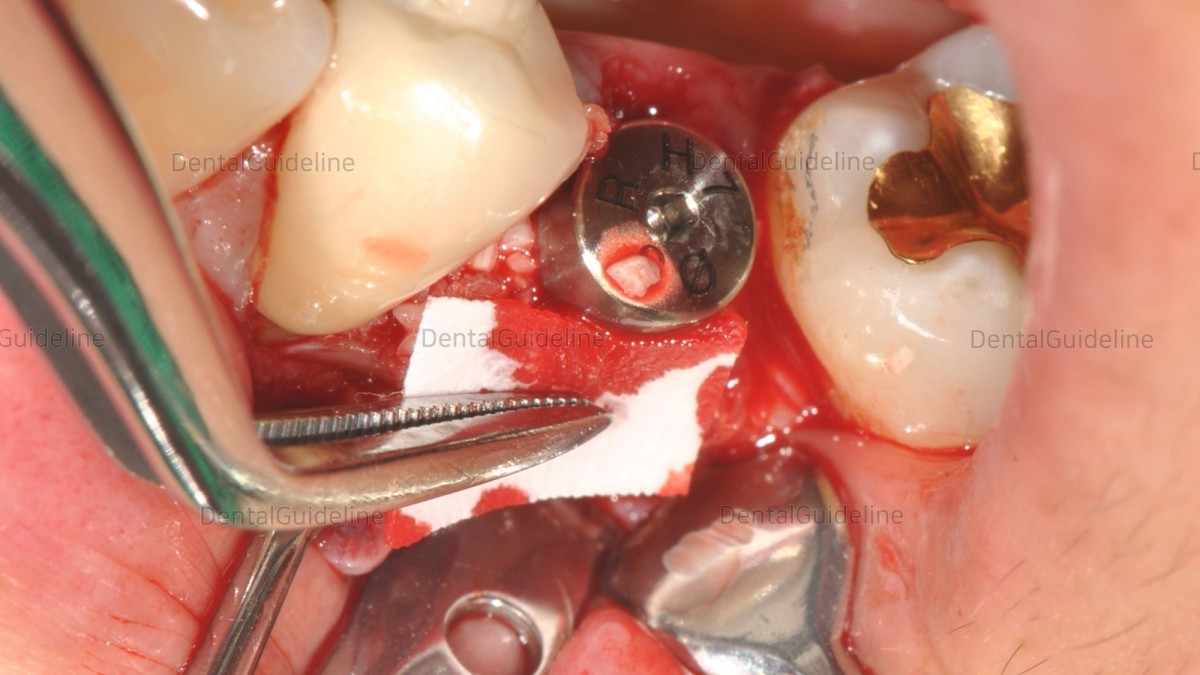

Remove the alveolar bone around the top of the implant that interferes with the HA connection using a bur.

Healing abutment connection.

GBR (FDBA, cortical)

Absorbable collagen membrane. (Lyoplant®)